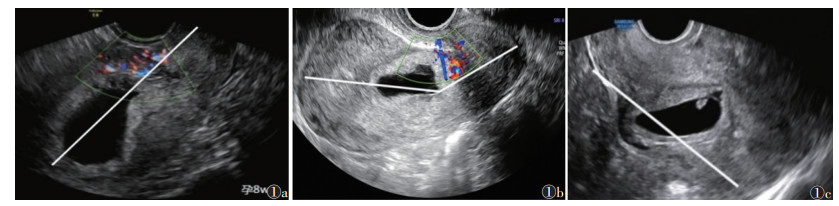

1.3.2 CSP分型标准① A型,妊娠囊最大部分穿过子宫腔/宫颈管(图 1a);②B型,妊娠囊最大部分嵌入子宫肌层,位于子宫内膜宫腔线和浆膜线之间(图 1b);③C型,妊娠囊穿过浆膜线,妊娠被一层薄薄的子宫肌层/内脏腹膜覆盖,并向膀胱子宫间隙或阔韧带突出[3](图 1c)。

| 注:图1a患者,女,32岁,孕7周2 d,妊娠囊最大部分向宫腔突出,为A型;图1b患者,女,30岁,孕6周5 d,妊娠囊最大部分嵌入子宫肌层,位于子宫内膜宫腔线和浆膜线之间,为B型;图1c患者,女,34岁,孕7周1 d,妊娠囊部分位于子宫轮廓之外,为C型 图 1 根据Delphi共识对剖宫产瘢痕妊娠(CSP)分型 |